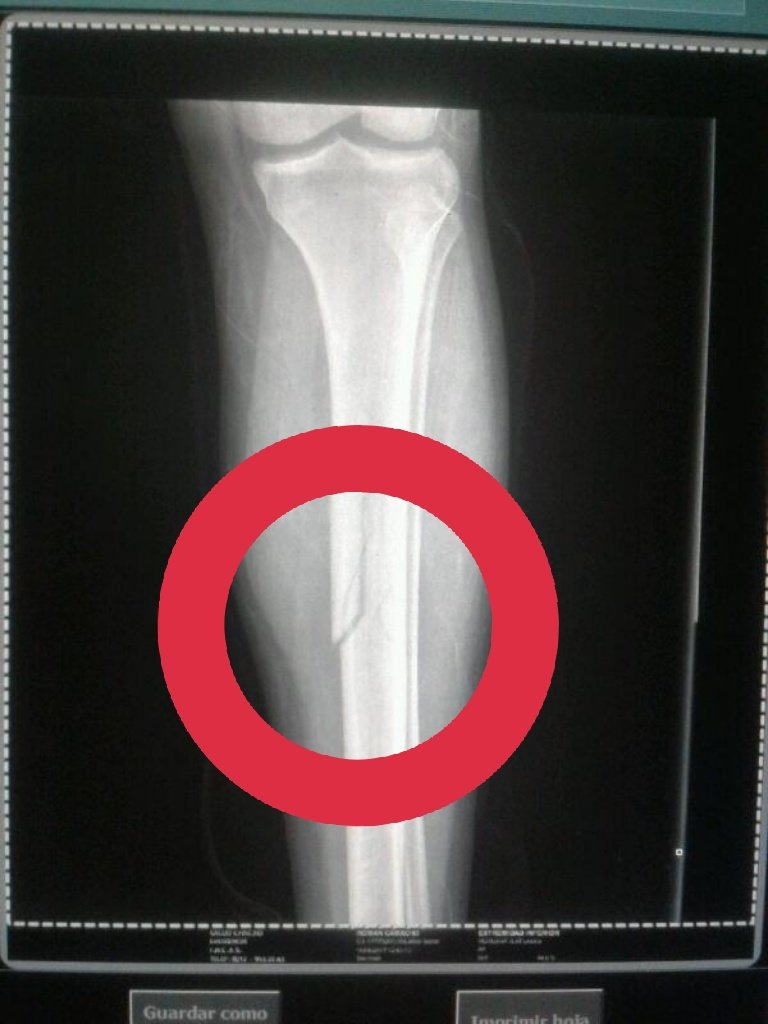

Al ser atendido en Salud Chacao le hicieron una placa en donde le diagnosticaron fractura en la tibia. Minutos más tarde fue trasladado a un centro de salud privado ubicado en el este de Caracas.

#ATENCION .@RCamachoVzla tiene fractura en la Tibia, al parecer producto de bomba lacrimógena a quema ropas, fotos @pamelatoledo28 #10abr pic.twitter.com/K68YV4St3y